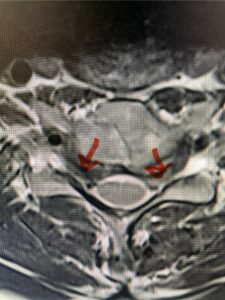

In this next case, this patient is a 47 year-old female who presents with intractable low back pain with severe pain, numbness, and weakness in the right lower extremity that had gotten progressively worse over a year. The patient had failed conservative management including physical therapy and epidurals. She was noted to have ⅘ weakness of plantar flexion. MRI demonstrated a large right L5-S1 disc herniation with severe compression of the descending right S1 nerve root (Fig 3). It was decided to perform a right L5-S1 hemilaminectomy for removal of the disc fragment and decompress the S1 nerve root. When you expose the disc, one must be certain to release any anterior adhesions to the nerve root in order to prevent a dural tear during retraction of the nerve root. It is also important to make sure during exposure and you finally encounter the dura after removing the ligamentum and fat, to make sure you are looking at the nerve root and not the main trunk of the thecal sac because if you don’t you can avulse or damage the nerve root if you retract the wrong structure.

Fig. 3a: Sagittal and axial T2-weighted lumbar MRI images demonstrating large right L5-S1 disc herniation (red arrows)

Fig. 3b